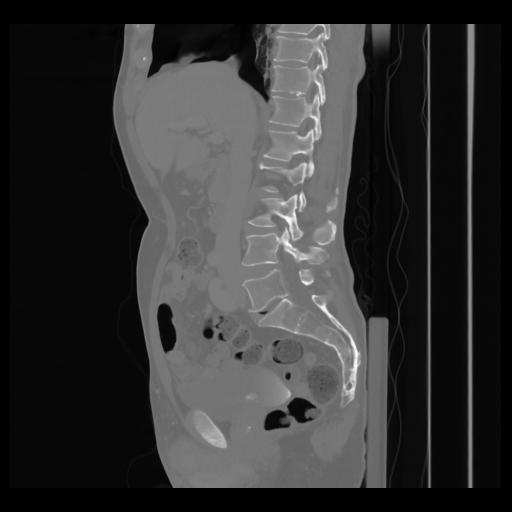

36 CUERPO,CE,Sagittal,3.000,CUERPO,Sagittal,